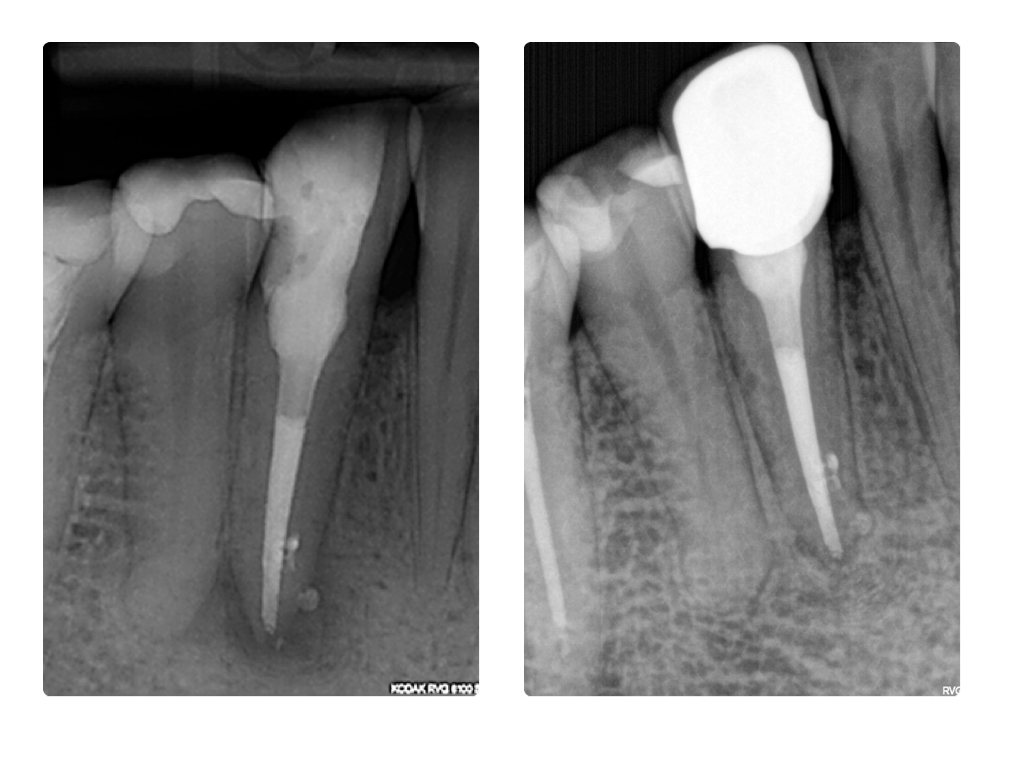

WS_Fallvorstellung8_15 8.003 Veröffentlicht 27. Juli 2015 am 1024 × 768 in Eckzahn im Recall 3 Monats und 9 Monatsrecall